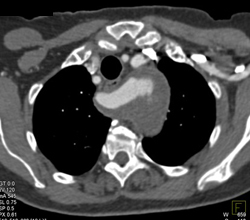

Superior Mesenteric Artery (SMA) Syndrome Sequence